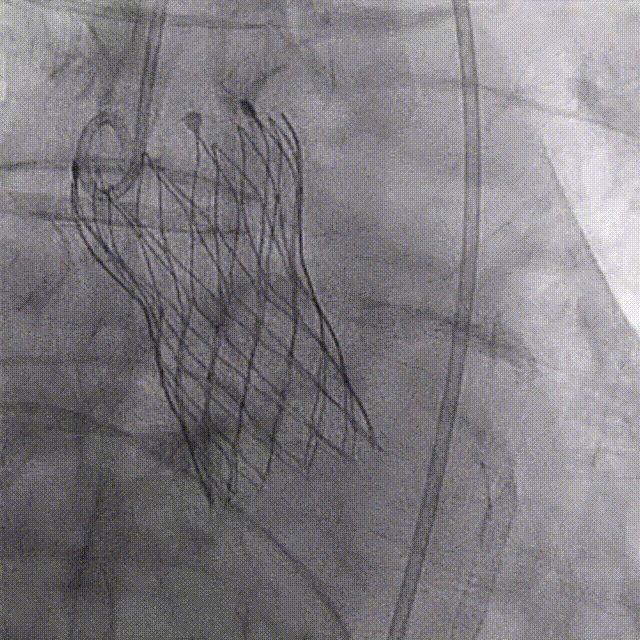

王焱教授展示了厦心医院已完成的5例机器人辅助TAVR手术的临床数据:该组患者平均年龄72.4岁,均为主动脉瓣重度狭窄。术后即刻技术成功率为100%,机器人完成的全部TAVR系统从进入人体到撤出过程,平均时长15分钟。目前5例患者均已完成30天随访,均无主要心脑血管事件的发生,人工瓣膜血流动力学指标符合治疗预期,无延迟的并发症出现。

术后即刻造影

该临床试验结果已初步展示出该系统的稳定性和优异性能。5例病例涵盖了常见的各种解剖类型,包含2例Type 1型二叶瓣,1例Type 0型二叶瓣,2例不同钙化程度的三叶瓣,钙化积分最低的仅92,最高的HU850积分达到了1560,涵盖了不同手术难度和解剖类型的病变。这些持续的临床结果为未来机器人辅助TAVR手术的可行性和安全性提供了坚实的证据。